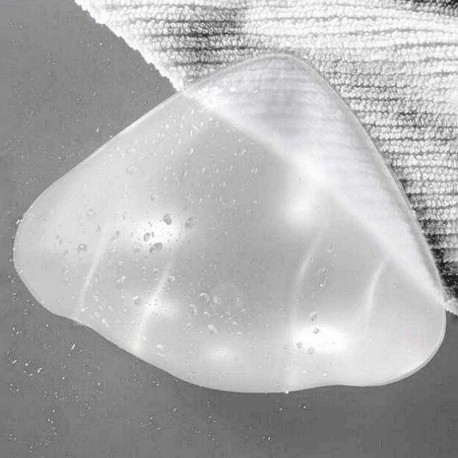

La forma simétrica está diseñada con ondulaciones en la cara interna así como extremo inferior, eliminando el 'efecto ventosa'.

Se presenta junto con una práctica bolsa impermeable, para transportar la prótesis Aqua Wave junto con un bañador húmedo..